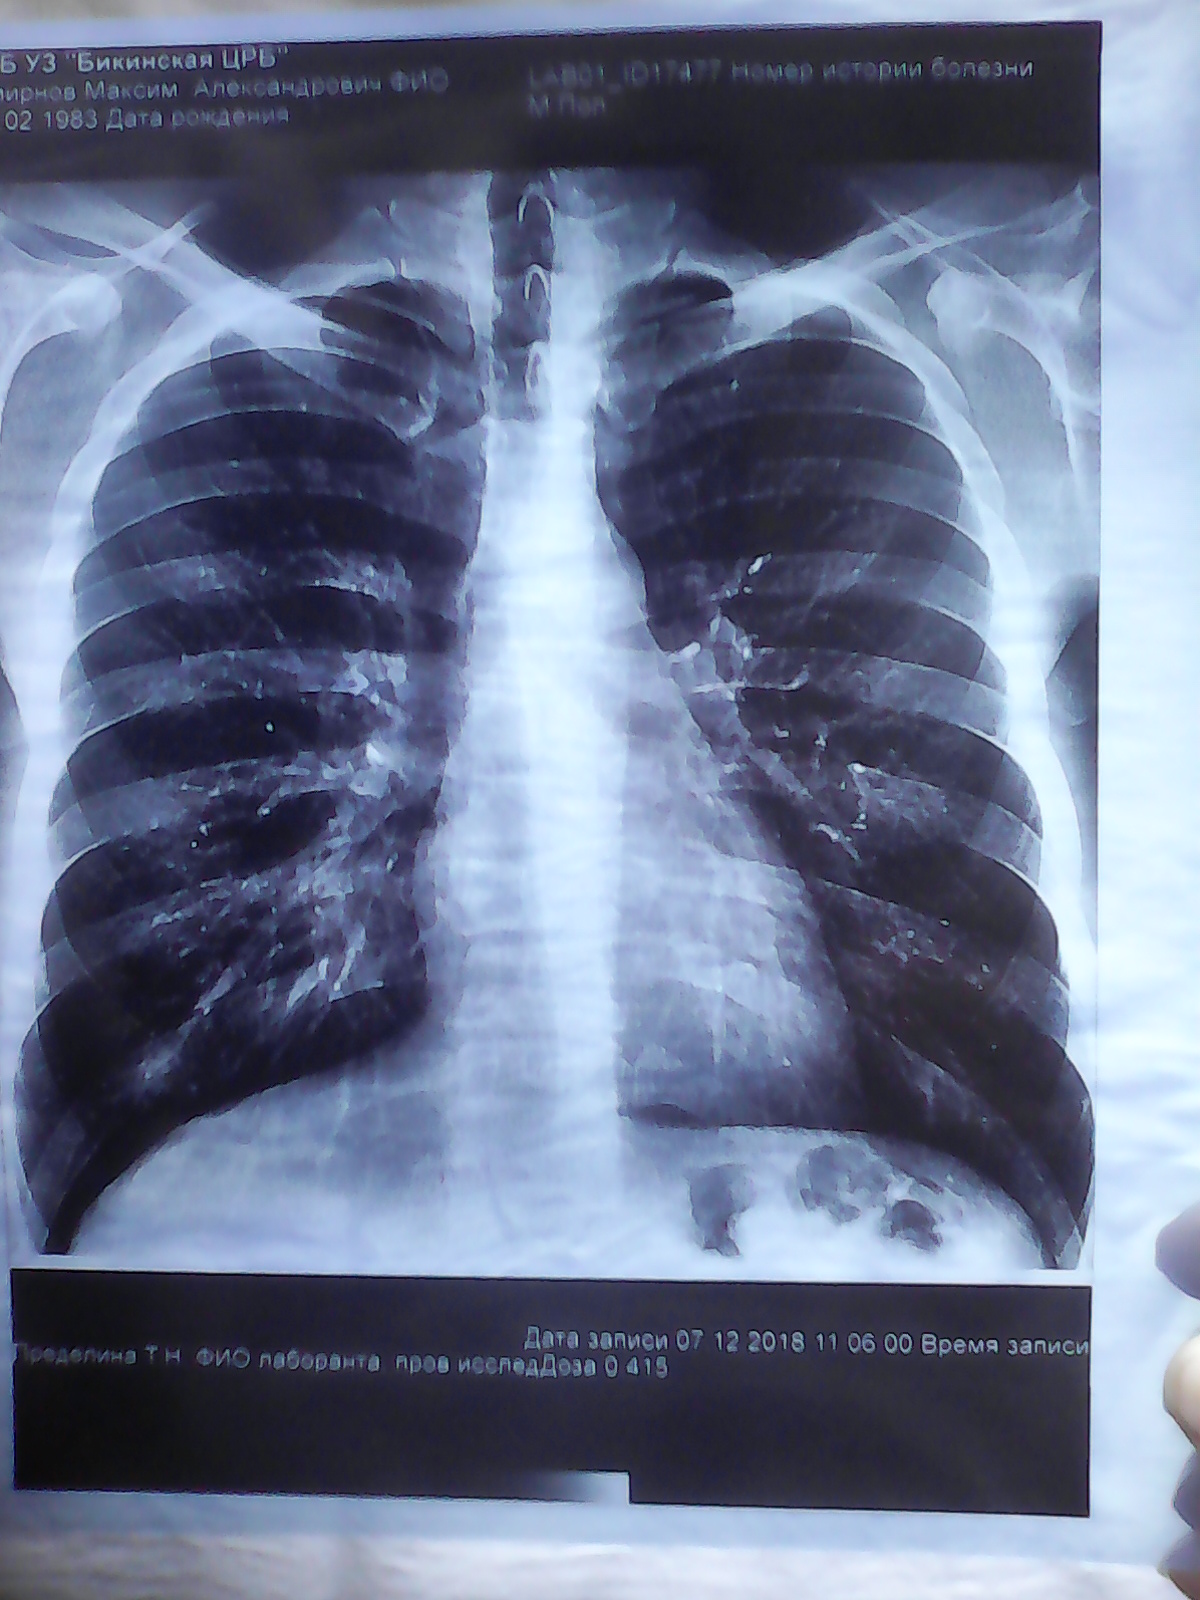

Снимок легких при туберкулезе является важным методом диагностики этого заболевания. На рентгеновских снимках можно увидеть изменения в легких, которые свойственны туберкулезу.

Рентгенография грудной клетки туберкулез

Рентгенография грудной клетки туберкулез

Рентген грудной клетки туберкулез

Рентген грудной клетки туберкулез

Фотографии снимков легких при туберкулезе

В данной статье представлены многочисленные фотографии снимков легких при туберкулезе, чтобы помочь вам понять, как выглядят изменения легких на рентгеновских снимках при этом заболевании.